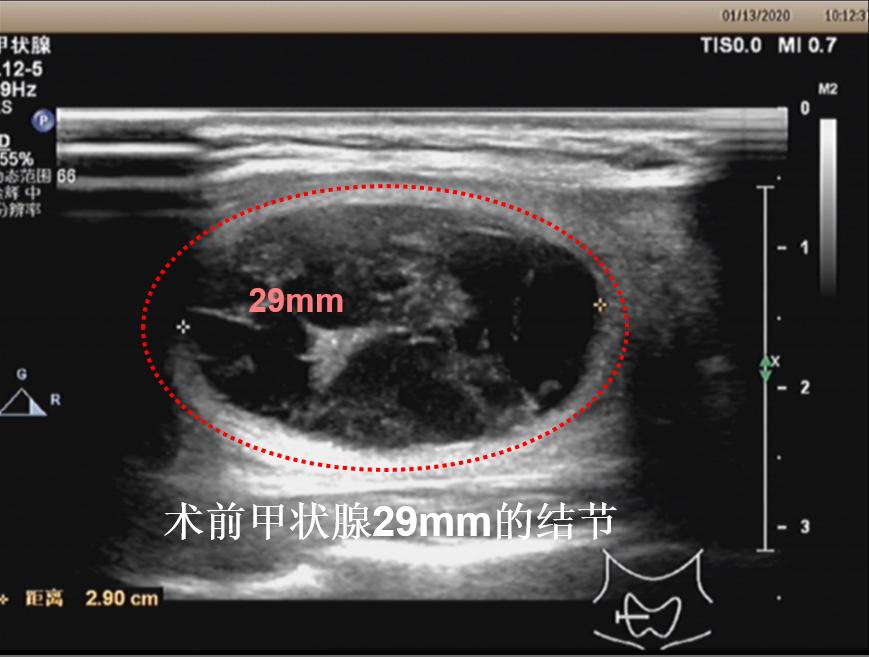

病例④: 3cm的甲状腺结节微创消融术后2月

微创消融前后超声对比,体积缩小99%